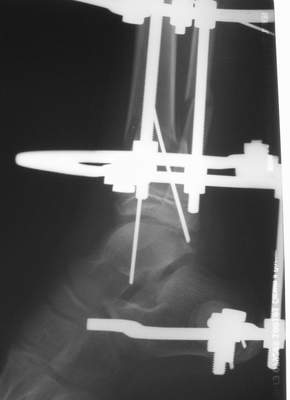

Нашел в комп-ре схожий случай:

1) з/репозиция, 2) фиксация 2 спицами, 3) аппарат, 4) фиксационные

спицы удалены...

См. аттачт.

А можно было наложить аппарат и по поводу ложного сустава...

По крайней мере не было бы укорочения (пусть и в 2 см)...